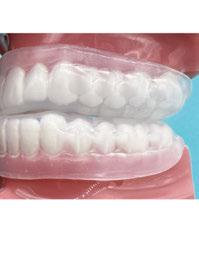

OPTISPLINT, by Digital Arches (https://digitalarches. com), is a dual-purpose implant coping, which serves as an abutment level scan body for fixed complete-arch prostheses as well as an analog verification jig. Individual scan bodies are inserted on each multi-unit abutment individually (Figure 4A). This scan body is unlike a traditional scan body, where a wing-like extension is cantilevered off of the scan region (Figure 3A). A central honeycomb metal frame piece is then placed, adjusted if necessary, within 1 mm-2 mm of wing components of the scan body (Figure 3B). Resin (flowable composite, dual-polymerizing, auto-polymerizing) or acrylic is then added to lute the scan bodies to the central honeycomb metal frame piece (Figure 4B). Once all scan bodies are attached, the OPTISPLINT jig can then be scanned as a single, splinted object, intraorally or extraorally (Figure 4C). If completed extraorally, the patient’s factors (blood, saliva, soft tissue, limited opening) are eliminated. An added benefit of this system is that the OPTISPLINT jig can then be poured in dental stone to facilitate the fabrication of an accurate master cast (Figures 5A and 5B). This is beneficial for checking the passivity of the prosthesis prior to inserting and can aid with the cementation of ti-bases to the interim or final prosthesis.

After all the records are acquired, the scans may then be aligned and the patient’s implant prosthesis can be designed and fabricated (Figures 7A-7F). The OPTISPLINT technique enables clinicians to utilize a fully-digital workflow for a fraction of the cost of other digital methods. Patient factors are able to be eliminated as the OPTISPLINT can be scanned extraorally with the added benefit of acting as a verification jig prior to prosthetic delivery.

Figures 5A-5B: 5A. Multi-unit analogs inserted into the OPTISPLINT jig. 5B. Stone verification jig created to aid in checking the passivity of the prosthesis

Figures 4A-4C: 4A. Individual scan body inserted into the multi-unit abutments. 4B. Central honeycomb piece attached to the scan bodies intraorally. 4C. Intraoral scan of OPTISPLINT jig